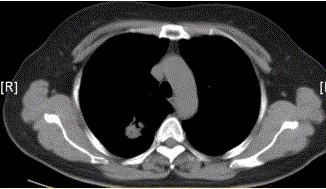

问题 患者女,54岁,无症状,常规体检透视时发现右上肺阴影。既往无结核病史。体格检查阴性。CT结果如下图。 易出现空洞的肺癌类型是

选项 A.鳞癌 B.腺癌 C.未分化癌 D.肺泡癌 E.转移性肿瘤 F.肺类癌

答案 A

解析 A